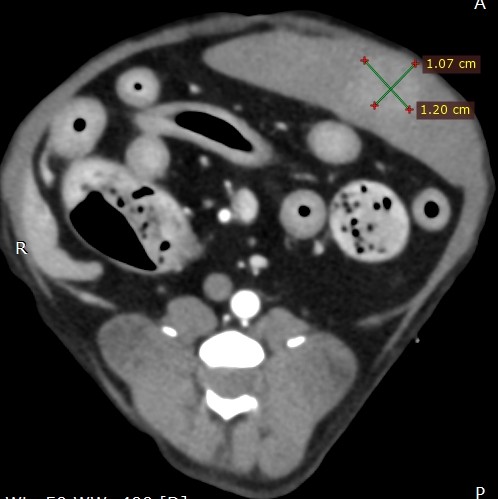

腹部超音波検査:肝臓、胆嚢、膵臓、腎臓、副腎、胃、小腸、大腸 = OK、しかし脾臓にφ1cmシコリ

念のため、CT検査をお勧めしました

数日後CT検査にて、

CT検査診断:脾臓に結節、胆泥症

この脾臓の結節、不気味です

手術をお勧めしました